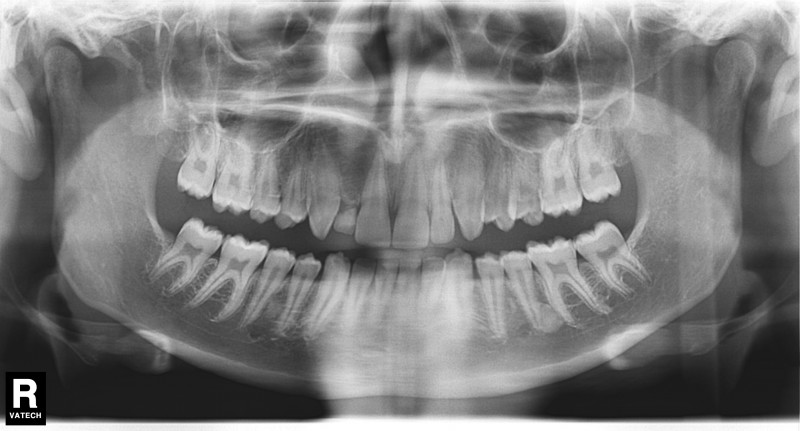

4. Ob jedem Weisheitszähne wachsen? Aber nein. Das hat aber nichts mit der einst vermuteten Reife zu tun.

Heutzutage haben etwa 20% der Erwachsenen überhaupt keine Weisheitszähne, sie haben also statt 32 nur 28 Zähne im Mund. Dies ist das Resultat einer Jahrtausende langen Evolution. Die Essgewohnheiten der Menschen hatten sich derart verändert, dass die hintersten Zähne, die normalerweise zuletzt durchbrechen, beim Verzehren der Nahrung überflüssig wurden, bzw. der Unterkiefer immer kleiner wurde, sodass die überflüssigen Achter irgendwann keinen Platz mehr haben.

Der aus dem Lateinischen stammende Begriff Weisheitszahn spielte darauf hin, dass damals, als die durchschnittliche Lebenserwartung eines Menschen noch viel niedriger lag als heute, das Durchbrechen der letzten Mahlzähne das Erwachsenenalter signalisierte. Heute wissen wir, dass die Weisheitszähne in vielen Fällen gar nicht so weise sind, denn auf Röntgenaufnahmen ist es ersichtlich, dass sie oft nicht richtig oder gar nicht durchbrechen, und entweder schief oder ganz quer im Kieferknochen stehen. Klingt nicht so weise, oder? Das ist in den meisten Fällen auch sehr schmerzhaft, daher werden sie operativ entfernt.